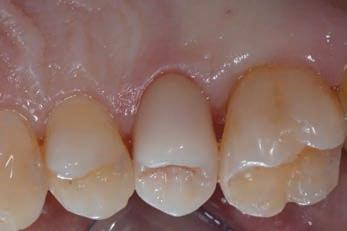

Figure 15, 16 &17: Views of the monolithic restoration in lithium disilicate, polished and finished.

Additionally, the ultra-thin structure of the Initial LiSi Block permits easily polishing of the restoration even after the occlusal adjustments, leaving the area extremely uniform and smooth. This reduces the finishing times, the brightness lasts longer and the occlusal contacts produce less abrasion of the restoration and of the antagonists (Figs. 15-17).